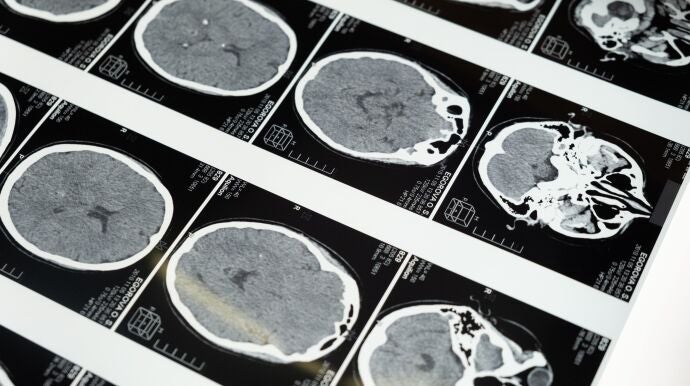

"Se estima que, en la actualidad, en España hay alrededor de 20.000 personas que padecen algún tipo de tumor cerebral, clasificado bien como un tumor primario (originado en el cerebro) o como un tumor metastásico (originado en otras partes del cuerpo, pero que se ha diseminado al cerebro)", informan los neurólogos.

Los tumores cerebrales suponen aproximadamente el 2% de todos los cánceres diagnosticados en adultos y el 15% de los diagnosticados en niños: es el segundo tipo de cáncer más detectado después de la leucemia, en la edad pediátrica.